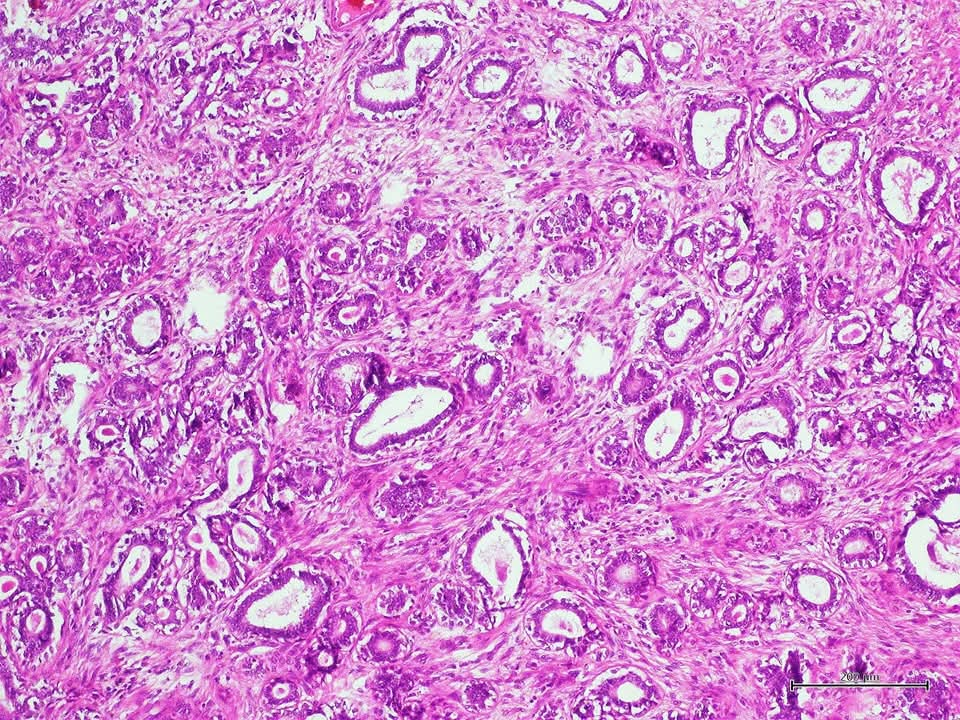

Regional lymph node metastasis of mucinous carcinoma, rectum with stage IIIC disease.

#pathology #GIPath #mucinous_carcinoma